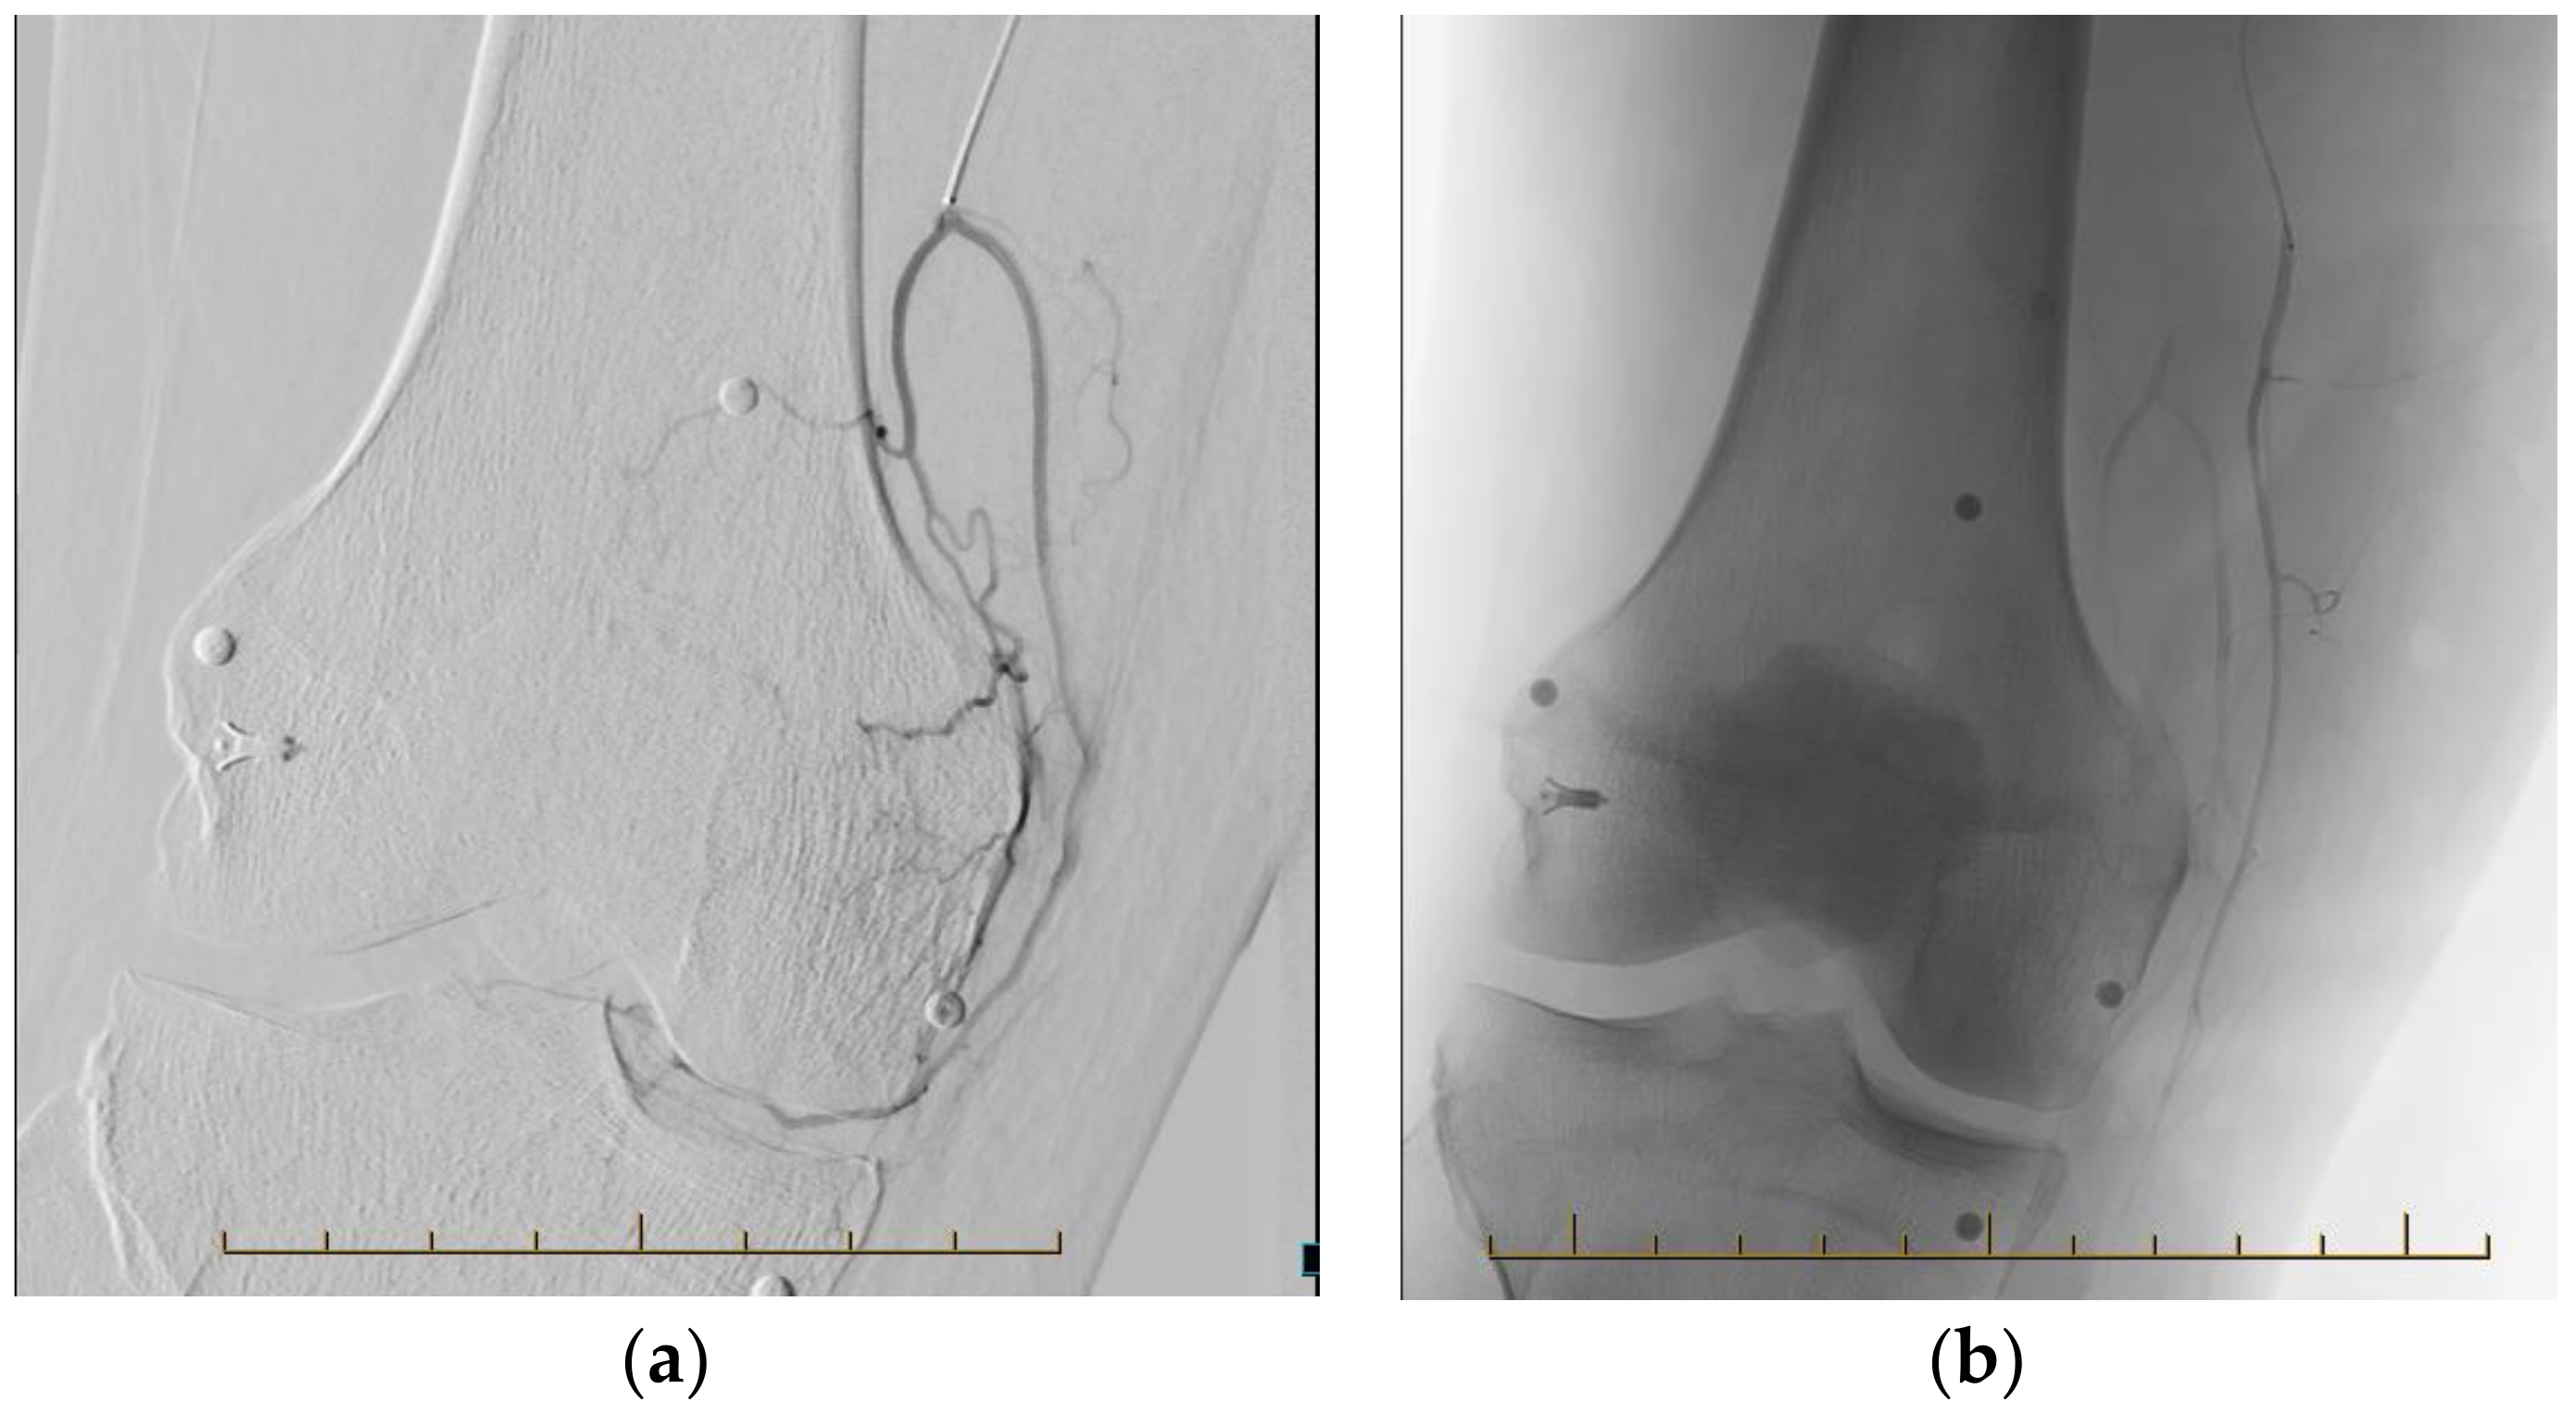

3.2. Procedural Technique